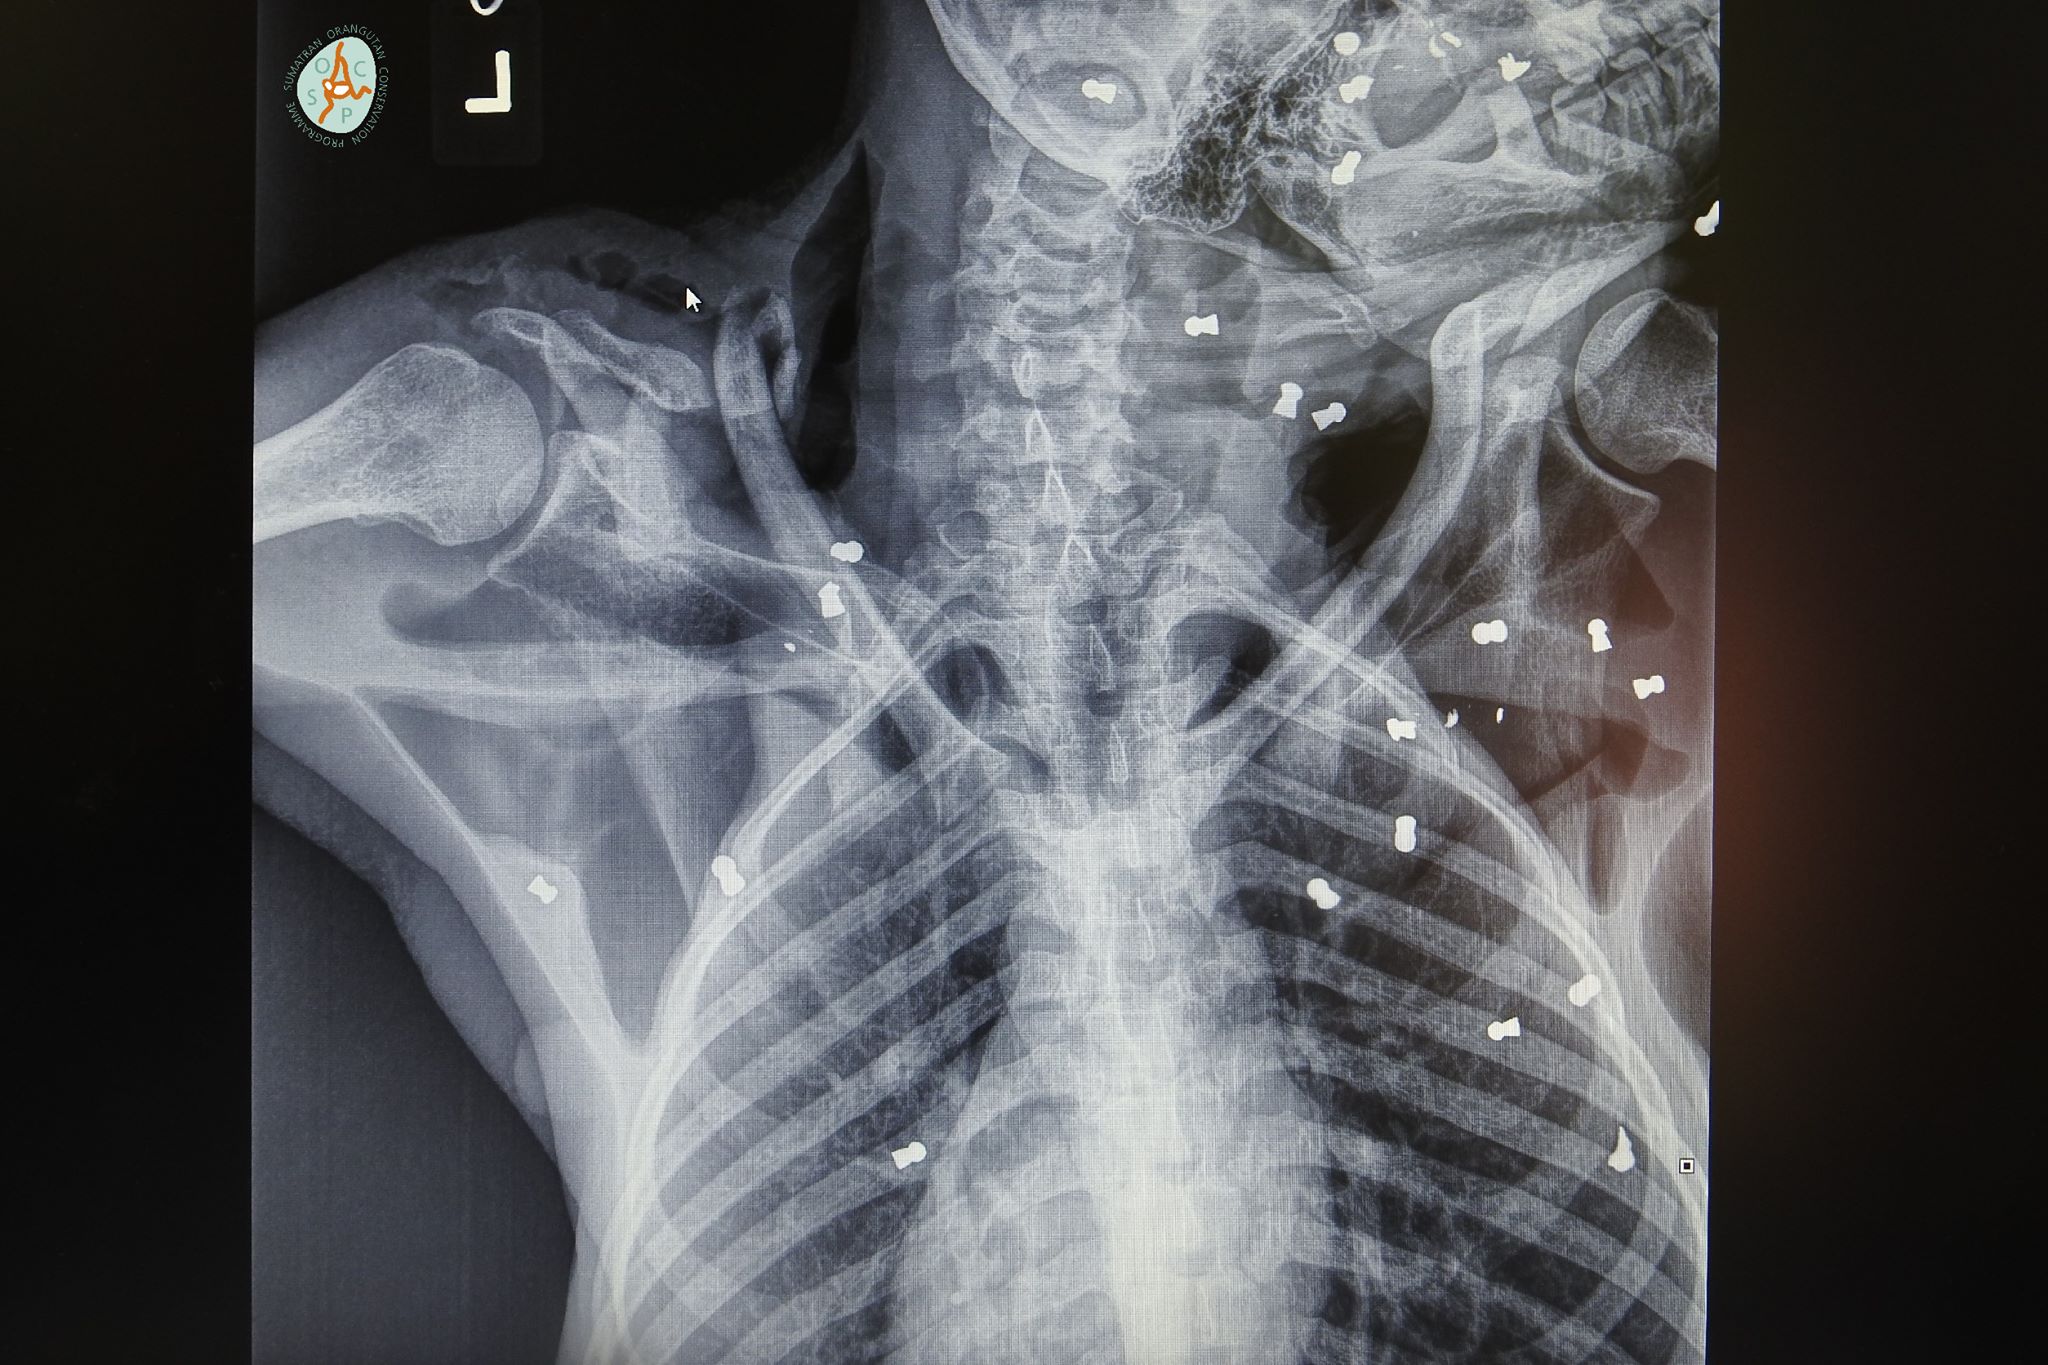

X-rays later revealed 74 air rifle bullets throughout her body, including in both eyes leaving her blind, as well as with broken bones. The severely wounded adult orangutan, named Hope by rescuers, was also nursing a seriously ill weeks-old baby when they were discovered in Aceh province’s Subulussalam district earlier this month.

Veterinarians went to work on 4-year-old Hope, removing pellets and fixing broken bones.